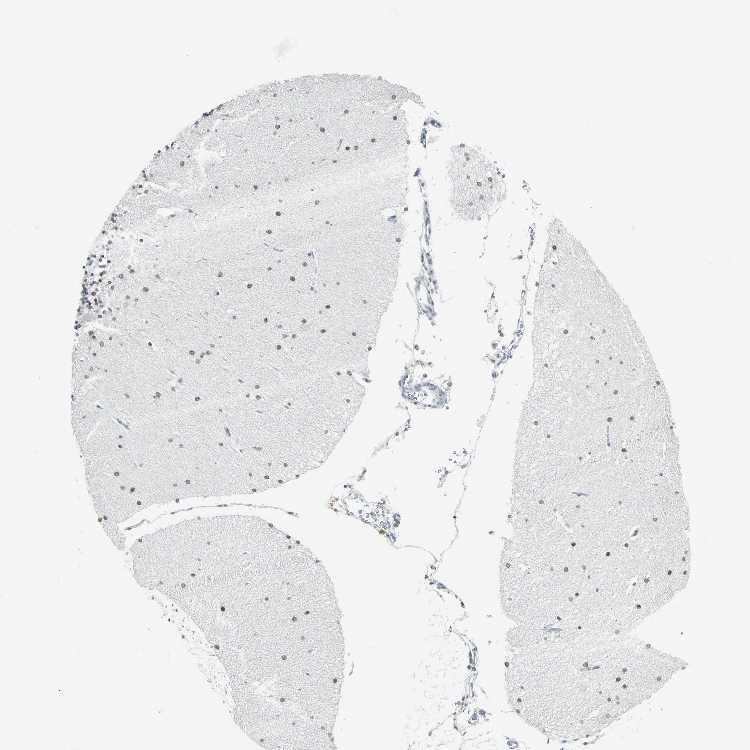

CEREBELLUM - Antibody stainingi

Antibody staining in the annotated cell types in the current human tissue is reported as not detected, low, medium, or high, based on conventional immunohistochemistry profiling in selected tissues. This score is based on the combination of the staining intensity and fraction of stained cells.

Each image is clickable and will lead to virtual microscopy that enables deeper exploration of all samples and also displays staining intensity scores, fraction scores and subcellular localization as well as patient and tissue information for each sample.

Antibody CAB005004

Cells in molecular layer Low